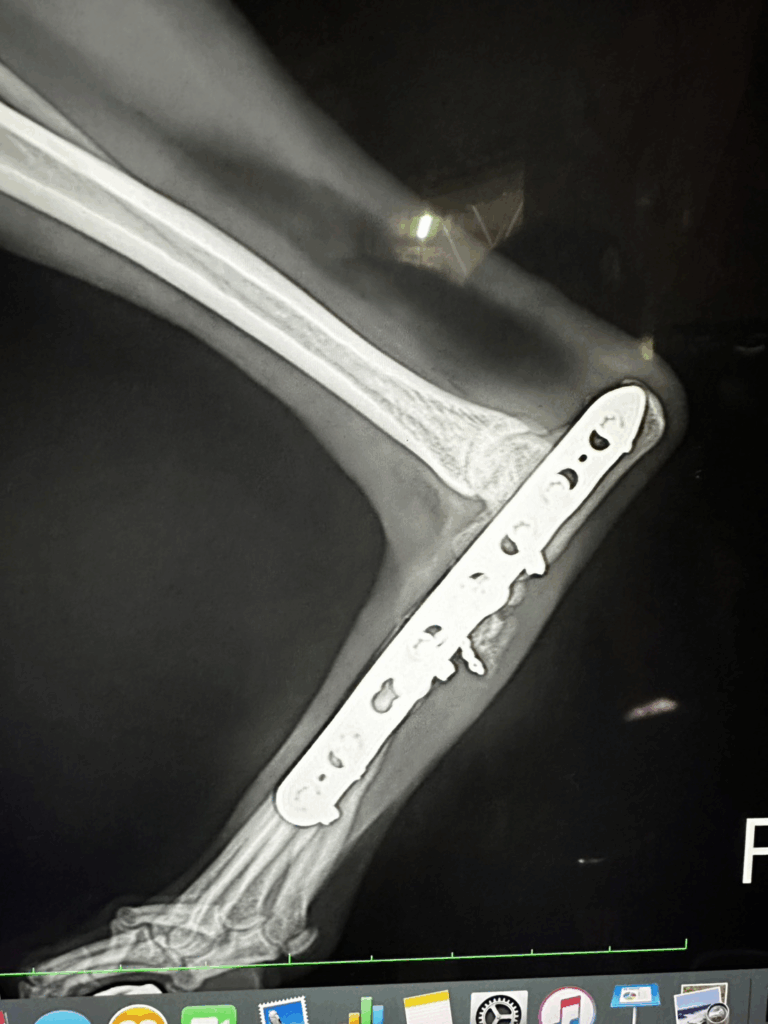

- 手術による整復と固定

- ピンやスクリューを用いた骨の安定化

- 手術後のリハビリ・再建トレーニング

特に重度の場合は、放置すると関節が変形して歩行困難になることもあるため、

早期の整形外科的治療が非常に重要です。